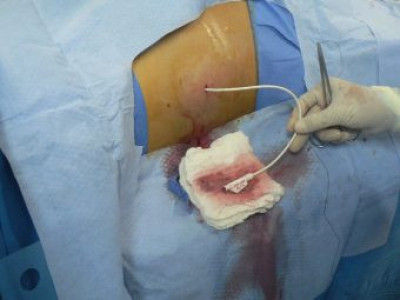

Drenaje percutáneo de absceso hepático

Envíado por Dr. Carlos Miguel Zavaleta Consuegra